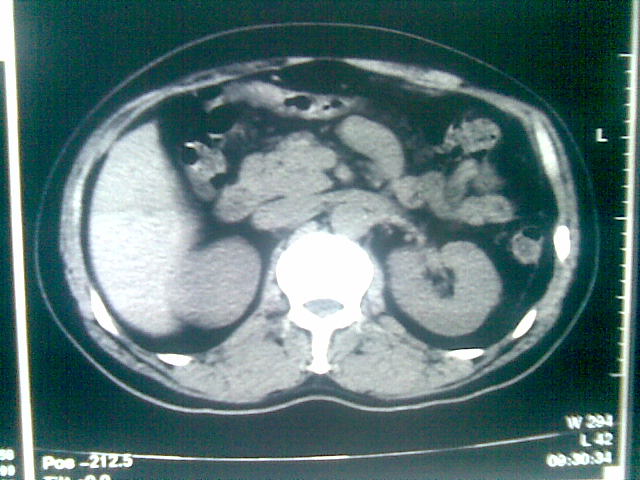

标题: CT23981:男,38岁阑尾炎术后透视胸腔积夜!做CT如下!积液包 [打印本页]

标题: CT23981:男,38岁阑尾炎术后透视胸腔积夜!做CT如下!积液包

可能与阑尾术后关系不太大,1.胸膜增厚粘连见少量气体。包裹脓气胸?左侧网膜囊脓肿?

少量积液部分粘连

左侧胸膜增厚、粘连+包裹液气胸。